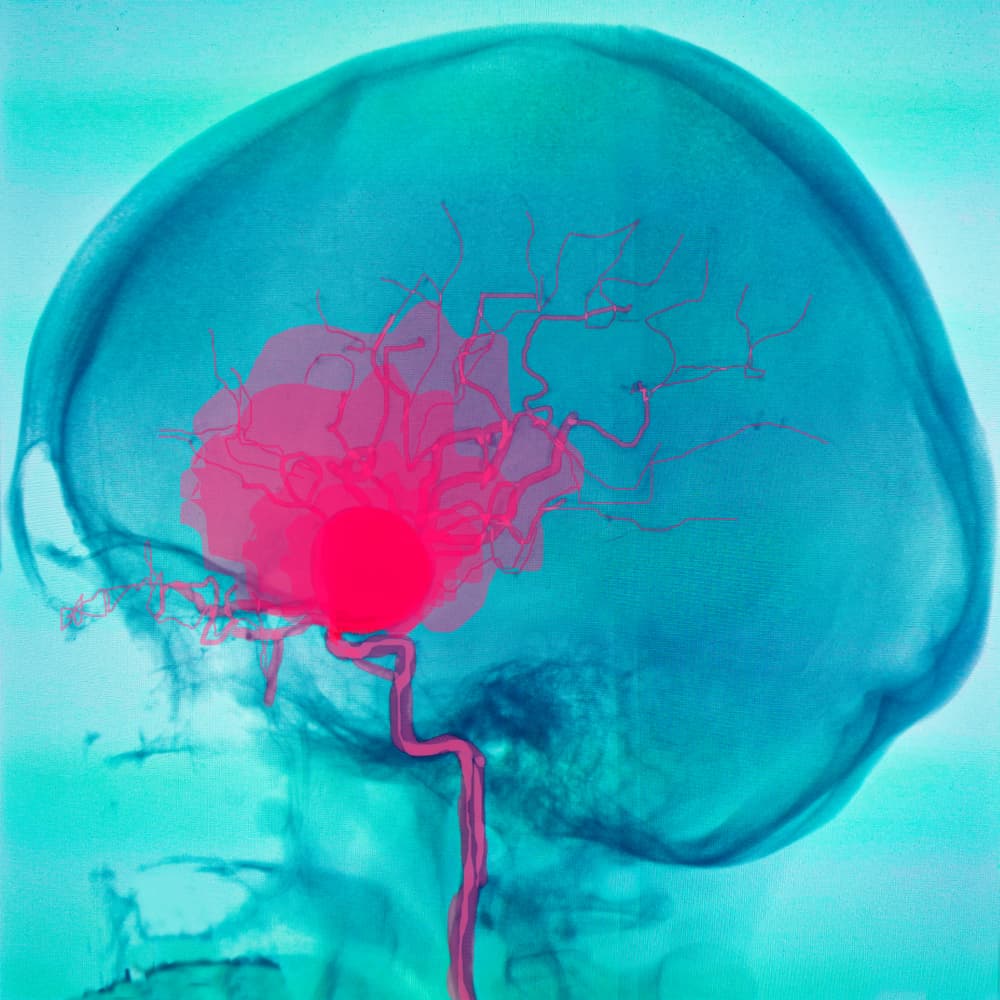

Un aneurisma es una dilatación en las paredes de un vaso sanguíneo. Es posible que esta dilatación permanezca igual por muchos años, sin llegar a romperse. El problema aparece cuando se rompe, porque puede causar un ACV provocado por un aneurisma, que fue el caso de esta mujer inglesa, de acuerdo a BMJ.

El ACV hemorrágico por aneurisma es un poco diferente del ACV más común: mientras que este último ocurre debido a un desbordamiento de la sangre en el cerebro por la rotura de un vaso sanguíneo (sin dilatación), el primero viene de un derrame en los vasos con características de aneurisma.

El primer tipo suele ser más grave y tener secuelas más preocupantes que el segundo. Cuando un aneurisma se rompe, la sangre se acumula en el espacio subaracnoideo, que está entre dos de las capas de las meninges: la piamadre (la más cercana al cerebro) y la aracnoides.

La acumulación de sangre en el espacio subaracnoideo deriva en hipertensión intracraniana, que debe ser controlada, ya que dificulta la llegada de sangre al tejido cerebral. En casos graves, esto puede causar muerte encefálica.

Este tipo de ACV es peligroso por el riesgo de nuevas roturas de vasos sanguíneos, y, en consecuencia, derrames de sangre. En caso de que esto acontezca, el riesgo de mortalidad es del 70 %. Por eso, se hacen necesarias cirugías para cerrar los aneurismas y disminuir las probabilidades de desarrollar complicaciones.